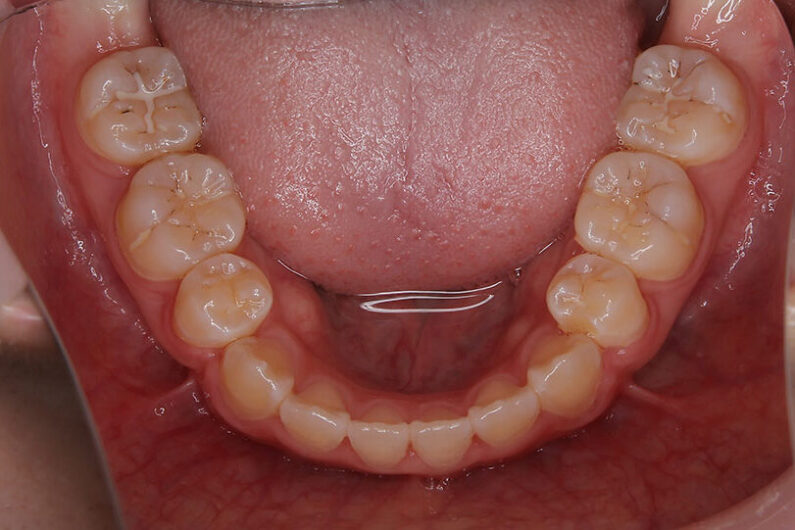

上顎前歯の強い叢生(がたつき)と、前歯部開咬状態でした。

装置撤去後1年10か月経過していますが安定しています。

マルチブラケット 動的治療期間 2年2か月 調整回数22回

口元、エステティックラインも下唇が下がり、良くなっています。